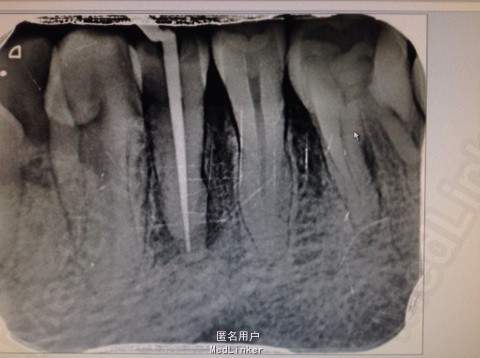

主诉:患者左下后牙胀痛数日。 病史:数日来,患者左下后牙食物嵌塞,近日疼痛不适影响进食,来院就诊。

查体:34牙合面无龋坏,探(-),冷热诊疼痛不明显,叩(+),颊侧可以可以看到窦道,X线示近中龋坏龋坏深达牙髓腔。远中及根尖有透色区。

诊断:34根尖周炎 治疗: 局麻下34去腐,开髓揭髓顶降牙合,冲洗髓腔,拔髓疏通根管,测量根管镍钛器械进行根管预备,低浓度次氯酸钠进行根管的冲洗化学预备,吸潮纸尖拭干根管,氢氧化钙进行诊间根管封药,对牙周进行洁治刮治,患者观察一周复诊,窦道明显的闭合,患者无不适感叩(-),去除暂封物进行根管试尖,X线示恰充,进行热牙胶垂直加压连续波充填法进行根管充填。暂封观察进行嵌体修复。